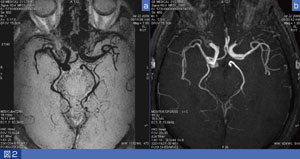

図2に、Cubeで撮像したblack blood (BB)MRAを示す。IC-PC動脈瘤の症例である。MinIP法を用いて、多方向からの観察が可能である。頭部MRAは、12chコイルで撮像できるので、スライス厚をさらに薄くしてもSNRに問題はない。

図2 Cubeで撮像した脳動脈瘤のblack blood MRAとTOF MRA a:Cube PD強調画像 b:3D TOF

a:Cube PD強調画像

b:3D TOF